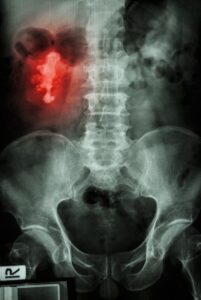

As pedras nos rins atingem cerca de uma em cada dez pessoas. Elas se desenvolvem principalmente a partir de cálcio e oxalato que vazam do sangue para a urina. (Os oxalatos são compostos naturais encontrados em plantas e humanos.)

Em quantidades maiores, o oxalato e o cálcio podem cristalizar e acumular-se formando uma pedra.

Os cálculos renais podem variar consideravelmente em tamanho, desde menos de um milímetro de largura até alguns centímetros.

Eles também podem ter formas incomuns: se a pedra se acumular nos canais ramificados (cálices) do rim, ela pode ter o formato de um chifre de um cervo.

Por isso é conhecido como cálculo “chifre de veado”.

Essas pedras causam problemas quando bloqueiam os ureteres, os dois tubos que transportam a urina dos rins para a bexiga. Se isso acontecer, pode causar fortes dores na região lombar, além de impedir o fluxo normal da urina. Isso pode causar infecção ou acúmulo de urina dentro e ao redor do rim.